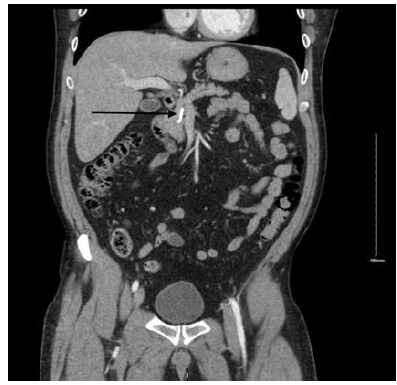

Figure 2: Broken Stent Neck of Pancreas

Figure 3: Stent Piece Neck of Pancreas